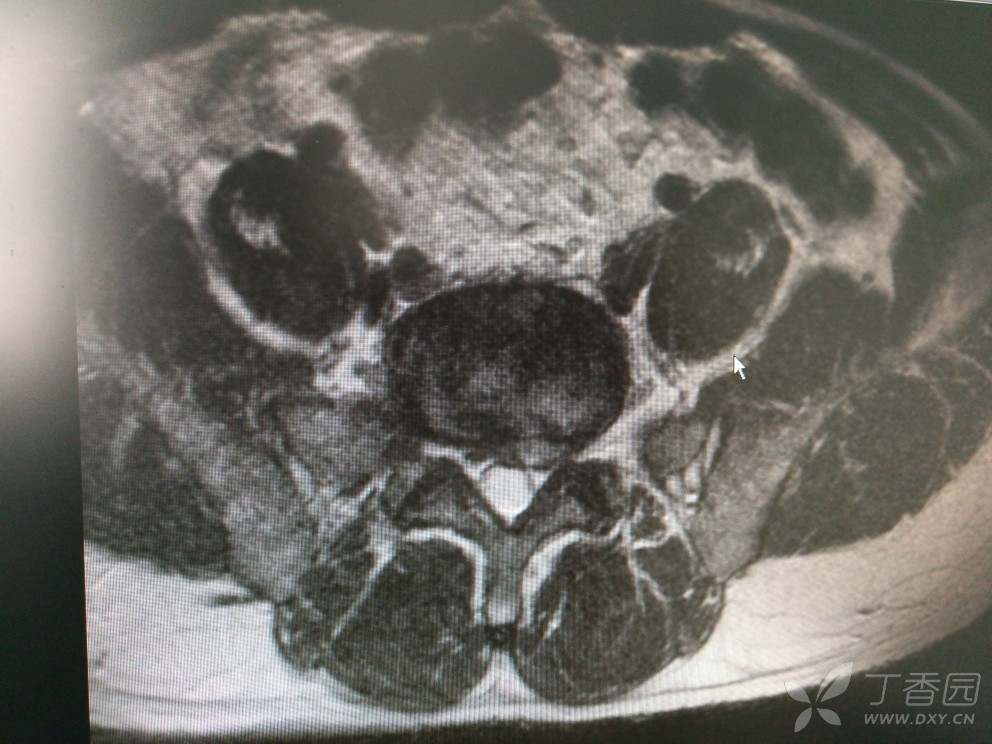

入院查MRI

我想问还是考虑L4/5 L5/S1椎间盘的变性引起的吗?